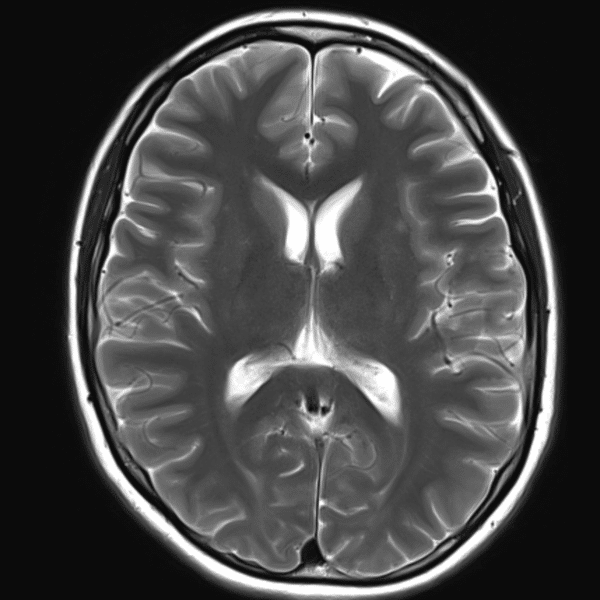

Brain T2WI

3.0T Siemens MAGNETOM Skyra

2D TSE

(L) 0.4×0.4×5.0 mm

(R) 0.4×0.4×5.0 mm

Conventional SwiftMR™ 02:22 01:09 (51% Faster)